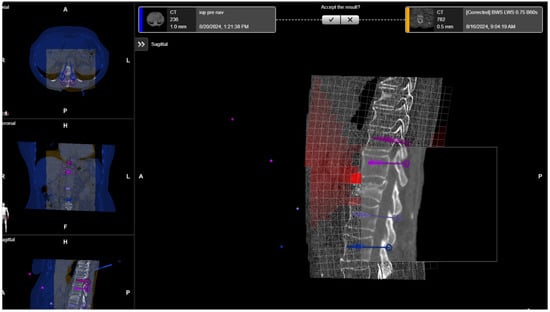

After selecting a region of interest (ROI), the iCT scan was merged with a preoperative scan. A rigid fusion was performed, and in cases of instability of the spine due to a tumor or fracture, as well as in cases of longer constructs, elastic fusion was performed (Figure 7 and Figure 8). In selected cases with longer thoracolumbosacral constructs, two scans were performed, with repositioning of the reference array to avoid compromising accuracy for levels far from the reference array. After fusion of the scans, the planned screw trajectories were checked and corrected as necessary (Figure 9) [4].

After placing the PSs, the surgical site was covered so that the reference array was visible for the navigation camera, and an iCT scan was performed to check the screw position (Figure 17). For longer constructs and spinal instability, the reference array for the second scan was repositioned so that the new scan could serve as both a control iCT scan for implanted screws and a registration scan for screws to be implanted. The second iCT scan is fused with the first registration scan to check the accuracy of screw placements and verify the deviation of the actual screws from the planned trajectories [4]. If the screws are misplaced, the misaligned screws can be segmented into the software to improve visualization after removal and implantation of new screws using the navigated technique. Repeated iCT scans show the visualization of the position of misplaced, repositioned, and corrected screws (Figure 18).